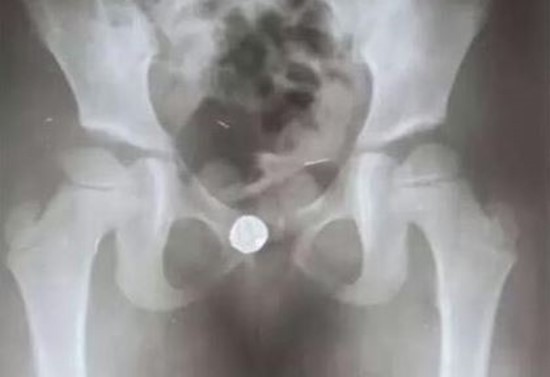

▲欣欣因為好奇貪玩,就將小鈴鐺塞進下體。(圖/翻攝自荔枝網)

起初醫生們都認為欣欣是陰道發炎或卵巢、子宮病變,家人一度還讓她輟學在家休養,沒想到情況不但沒有改善,分泌物反而還開始出現血絲。後來有醫生做超音波時聽到不規則的回聲,懷疑可能是下體有異物,於是改安排照X光,果然在欣欣的陰道內發現一顆小鈴鐺。